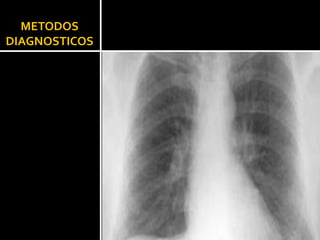

METODOS  DIAGNOSTICOS

Rx TORAX